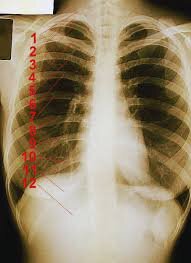

Мужская рентгенограмма, стрелками указаны задние и передние дуги 1-3 рёбер, цифры с 4 по 12 проставлены на задних дугах соответствующих рёбер.

Рёбра всегда считаются сверху, то есть сначала нужно найти первое ребро, а потом уже до него досчитать до интересующего нас места. По крайней мере нас так учили.

Но отыскать первое ребро - самая большая засада. Чаще всего за него принимают ключицу.

Задняя дуга рёбер видна лучше, чем передняя, что объясняется достаточно просто - задняя дуга целиком костная, передняя в значительной части - хрящ. Обратите внимание на еще одну засаду - толкучку в районе 1, 2 и 3 рёбер. Это связано с разными углами наклона и особенностями проецирования всего этого объемного безобразия на плоскость.

Пересчет ребёр не оставляет сомнений в том, что и на первом снимке, и на втором их ровно 24 штуки.